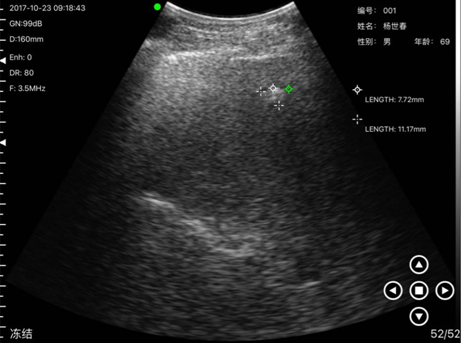

病例3姓名:杨x春,性别:男,年龄69岁,通过掌上B超设备检测发现其肝部有异物,到沙县医院复诊确诊为肝血管瘤。